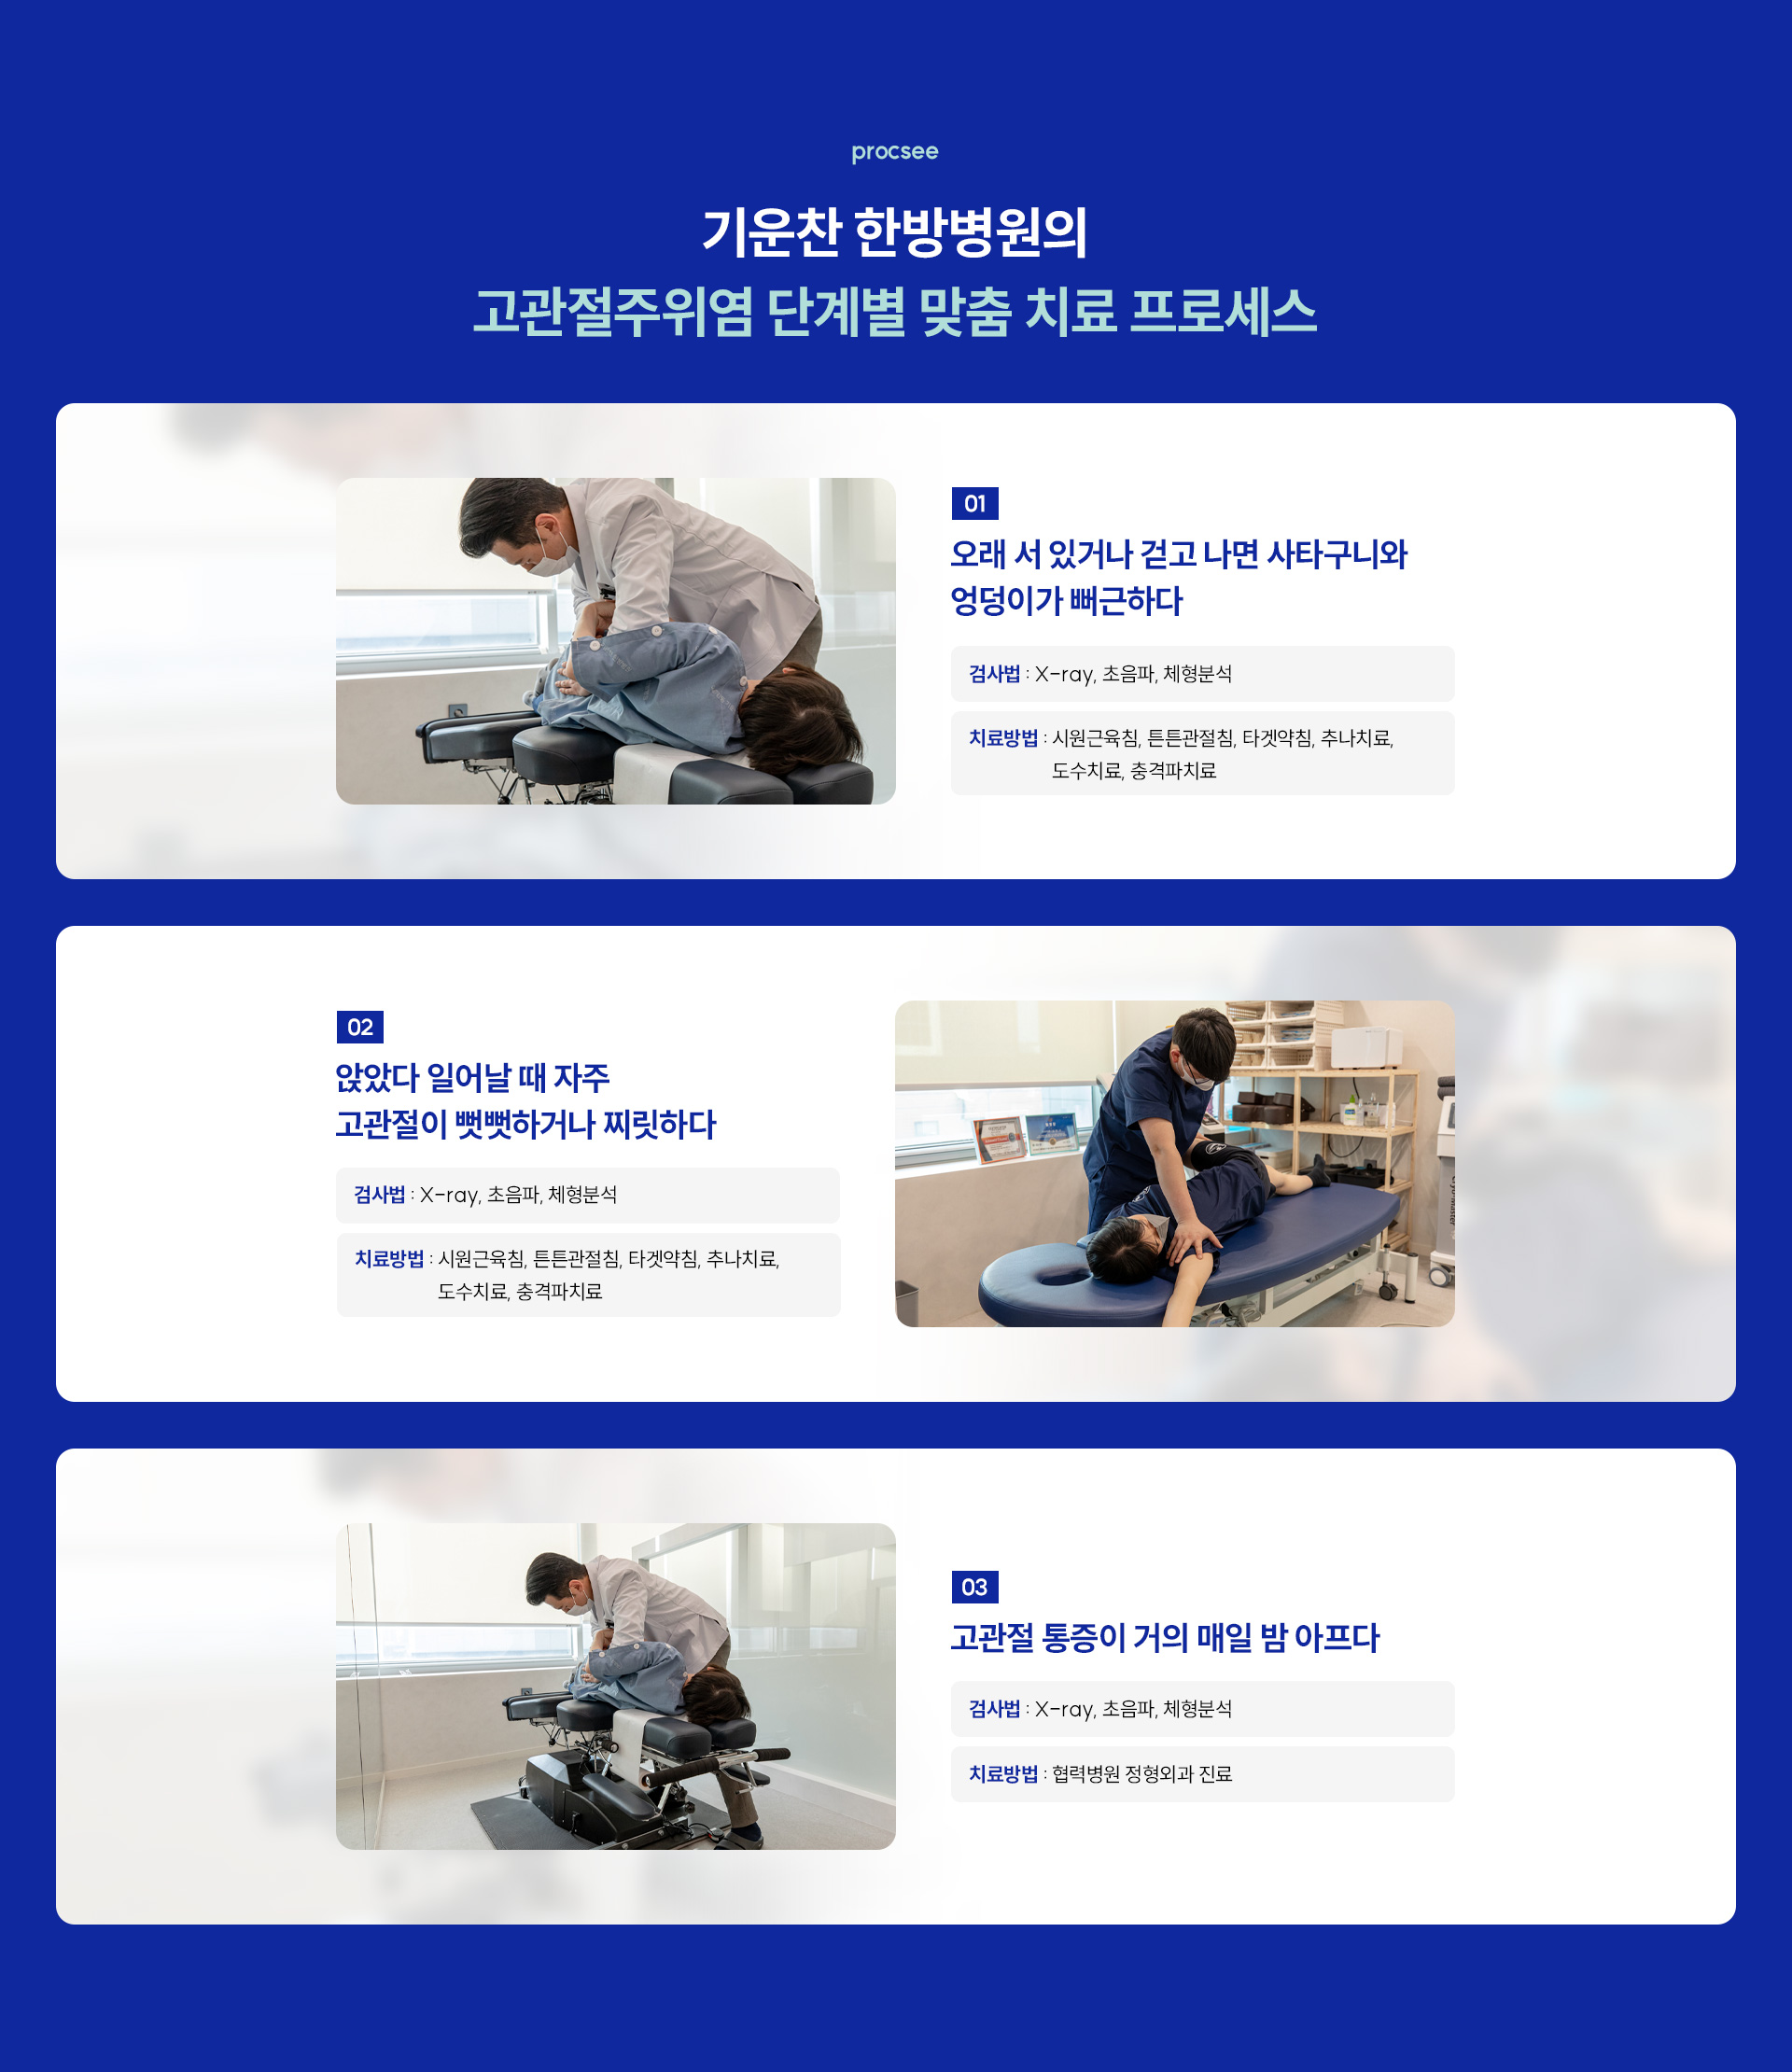

고관절주위염은 추나치료, 침치료, 약침치료를 통해 염증을 효과적으로 완화할 수 있습니다.

기운찬한방병원에서는 신체의 회복력을 기반으로 한 비수술적 치료를 시행하며,

스테로이드 약물을 사용하지 않고도 증상을 개선할 수 있는 것이 큰 장점입니다.